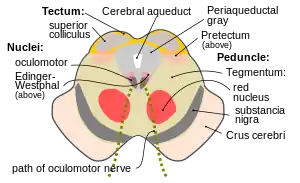

Section through superior colliculus showing path of oculomotor nerve. | |

Transverse section through mid-brain; number 2 indicates the cerebral aqueduct.

Transverse section through mid-brain; number 2 indicates the cerebral aqueduct. Transverse section of mid-brain at level of inferior colliculi.

Transverse section of mid-brain at level of inferior colliculi. Transverse section of mid-brain at level of superior colliculi.